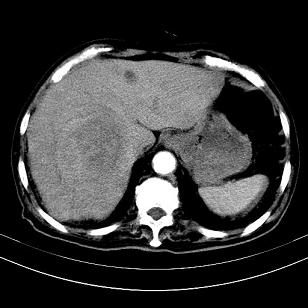

标题: CT19407:肝内还是肝外原发性肿瘤??

男,63岁,高血压病史40余年,

考虑右肝后叶肝癌(部分外生)伴肝内多发性转移;右侧肾上腺区恶性肿瘤并肝转移待排。

考虑右肝后叶肝癌(部分外生)伴肝内多发性转移

考虑肝右叶变异肝癌并肝内转移

支持肝右叶巨块型肝癌伴肝内转移.

考虑右肝后叶肝癌(外生型)伴肝内转移。

肝右叶外生性肝癌,伴肝内转移

支持肝右叶巨块型肝癌伴肝内转移。

考虑肝右后叶肝癌(部分外生)伴肝内多发性转移;不排除右侧肾上腺区恶性嗜铬细胞瘤并肝转移。